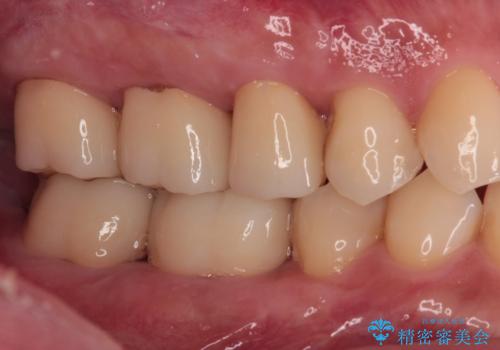

痛くてかめない 根管治療とオールセラミッククラウン

- 右上の小臼歯部に咬んだときに強い痛みを感じるとのことで来院された患者様です。

診査を行った結果、根管治療を行った後にオールセラミッククラウンにて補綴する治療計画となりました。

咬んだときの痛みに加えて夜間のズキズキする痛みもありましたが、1回目の根管治療実施後間もなく咬んだときの痛みがなくなったので、2回目に根管充填を行いました。